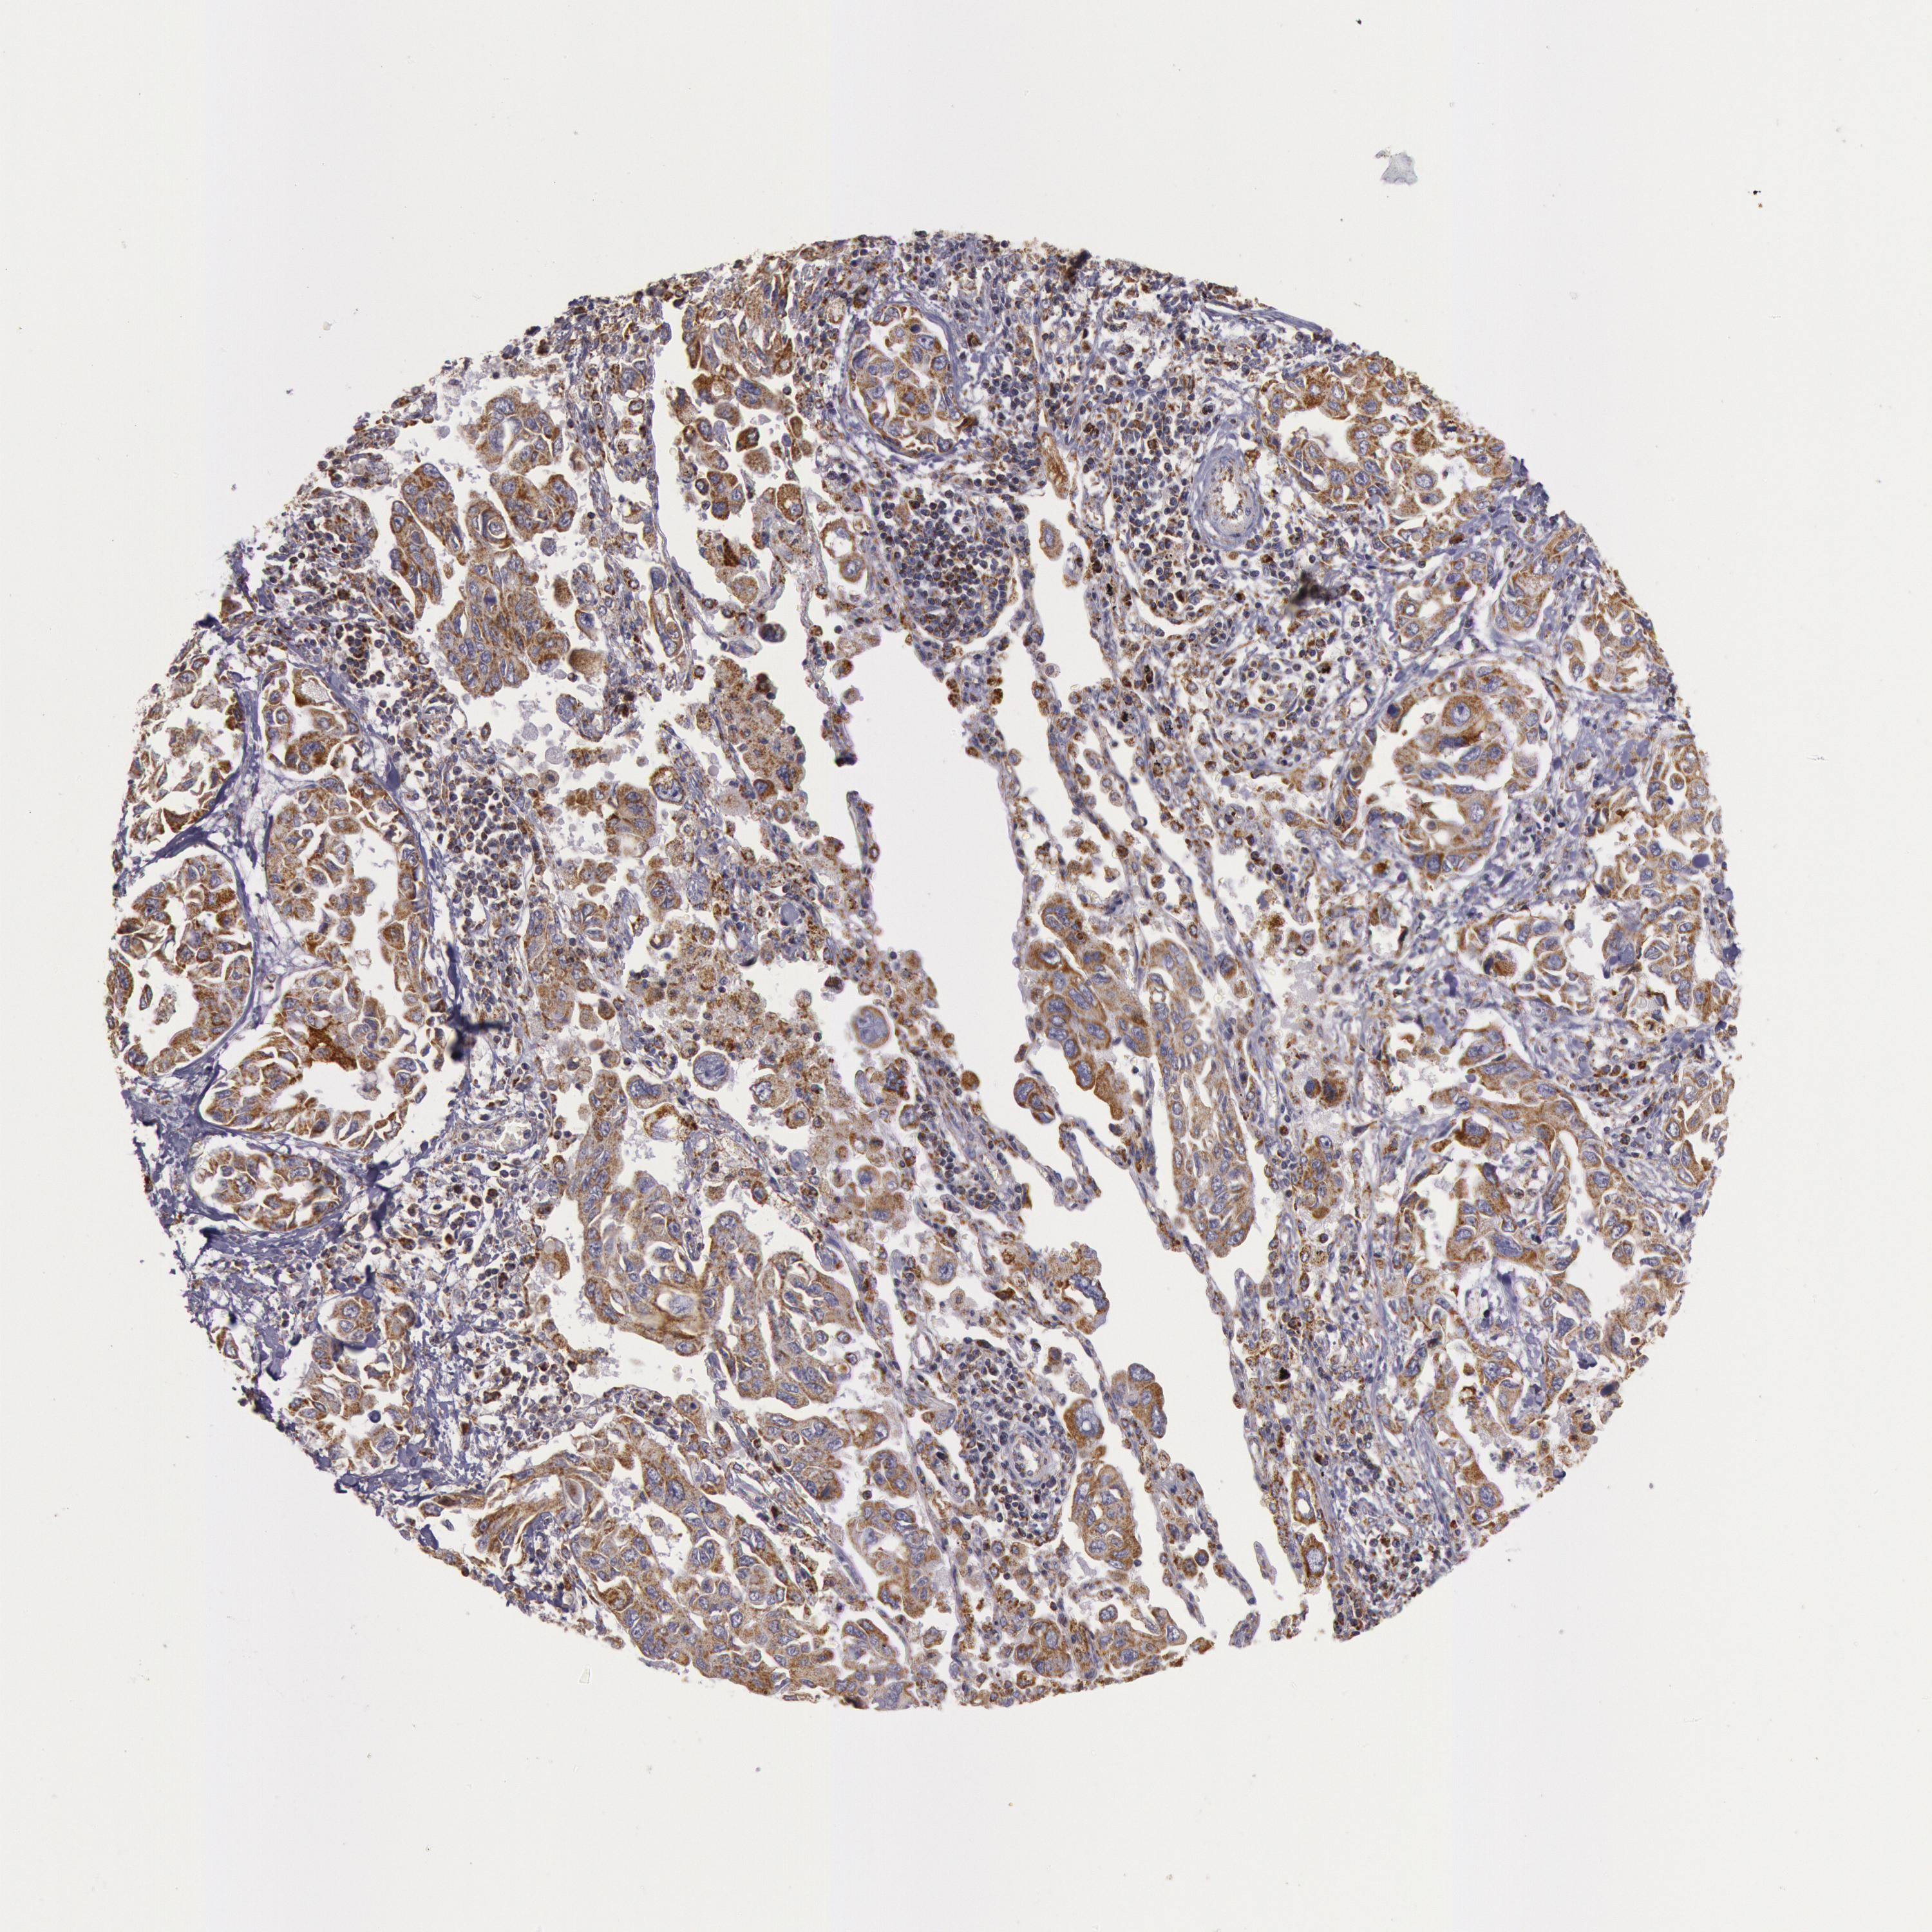

CANCER LUNG CANCER Show tissue menu

LUAD TCGA LUAD VALIDATION LUSC TCGA LUSC VALIDATION PROTEIN LUAD CPTAC PROTEIN LUSC CPTAC PROTEIN EXPRESSION

ANTIBODIES

AND

VALIDATION